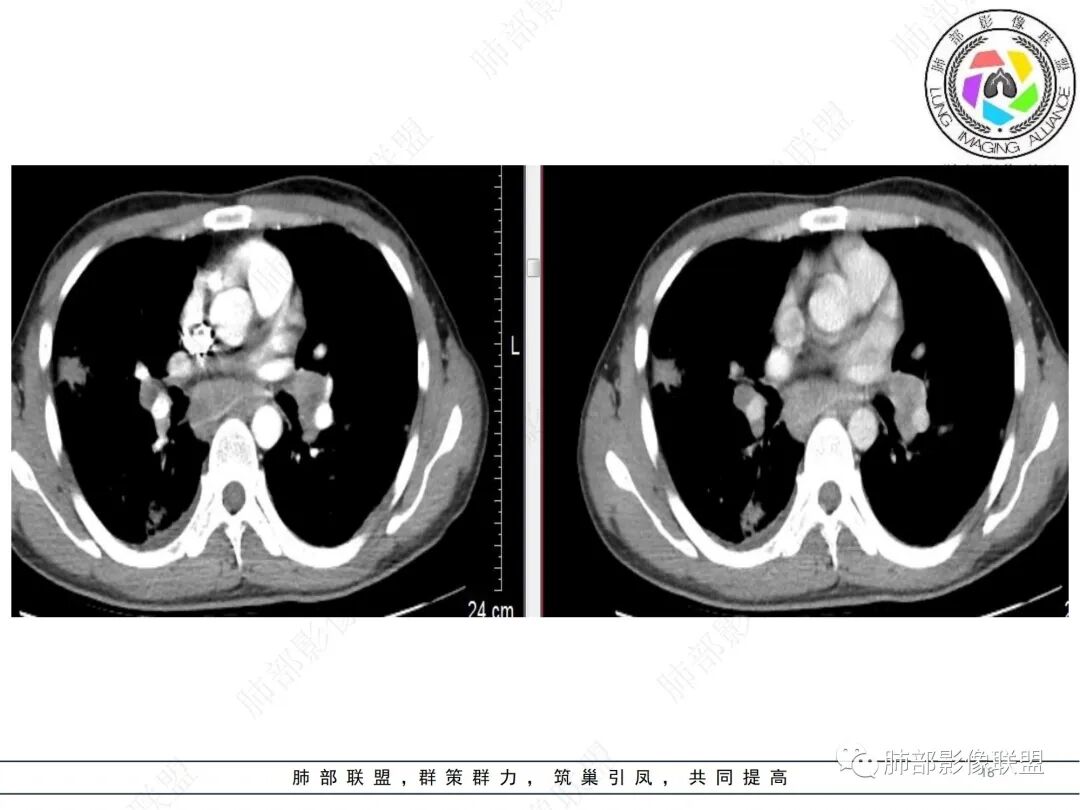

男,35,咳嗽、咳痰1周。胸部CT:两肺多发团片影,大部分沿胸膜下分布,支气管穿行;周围可见簇状小结节影,沿中轴间质分布;双侧肺门及纵隔淋巴结肿大。增强轻度强化,部分层面可见血管飘浮。考虑淋巴道增殖性病变,淋巴瘤?LYG?鉴别TB、结节病等。

肺内病灶有沿淋巴间质分布的特点,后纵隔融合肿块见血管漂浮征,这些支持,但没有发热肝脾肿大,浅表淋巴结肿大等其他特点,可能性就减小了。

双肺表现及纵隔淋巴结表现需要考虑,但男性发病率相对较低,且淋巴结内出现明显血管漂浮(结节病为非干酪样坏死,中间应该不会有明显血管出现),这样可能性也小了。

2.影像特点:双肺多发实变,结节状、斑片状、斑点状影,成簇分布趋势,密度不均(部分密度较高),多数位于胸膜下或支气管血管束周围,与支气管关系密切,部分气管壁钙化,部分实变影周围多发弥漫粟粒结节呈星系征样改变,呈轻度渐进性强化,未见空洞。双肺门及纵隔淋巴结肿大,并显示融合,其中后纵隔肿大淋巴结间可见血管影穿行。右侧胸膜增厚伴少量胸腔积液。

3.病例小结:男,35岁,咳嗽咳痰一周,胸部CT提示:双肺多形、多态、多部位的分布,淋巴结肿大,胸膜增厚、胸腔积液,气管壁关系密切,这些可符合结核。

年轻患者,无免疫缺陷,继发性肺结核很少侵犯淋巴结,且无TB中毒症状,双肺门及纵隔淋巴结肿大,应想到结节病可能,不典型之处在于,小叶间隔、叶间裂、血管支气管束较少观察到串珠状小结节影,胸膜增厚伴积液也很少见于结节病。